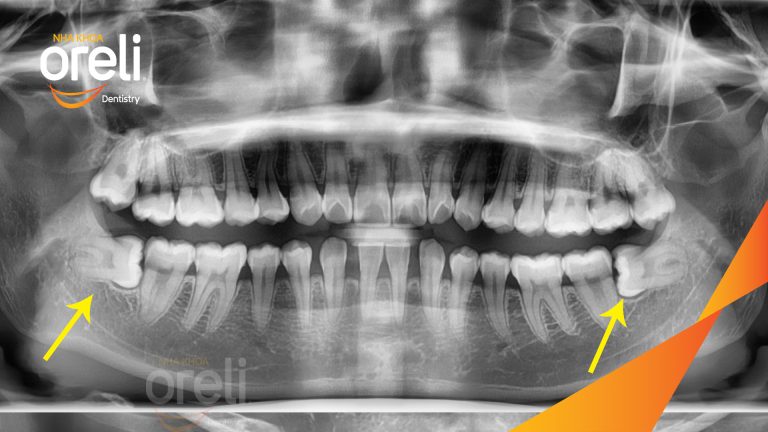

Nhổ răng khôn hai hàm do chen chúc – Ca thực tế tại Oreli

Nhổ răng khôn

Mọc lệch